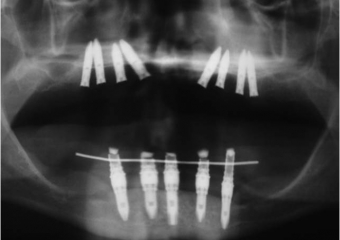

Raio X inicial

Rx do enxerto ósseo de maxila, com osso de crista ilíaca

Rx dos implantes Cone Morse superiores